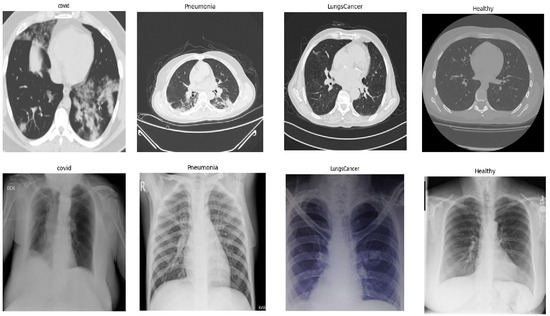

Comparison Between Early and Intermediate Fusion of Multimodal Techniques: Lung Disease Diagnosis

by Ahad Alloqmani and Yoosef B. Abushark

AI 2026, 7(1), 16; https://doi.org/10.3390/ai7010016 - 7 Jan 2026

Early and accurate diagnosis of lung diseases is essential for effective treatment and patient management. Conventional diagnostic models trained on a single data type often miss important clinical information. This study explored a multimodal deep learning framework that integrates cough sounds, chest radiograph [...] Read more.

Early and accurate diagnosis of lung diseases is essential for effective treatment and patient management. Conventional diagnostic models trained on a single data type often miss important clinical information. This study explored a multimodal deep learning framework that integrates cough sounds, chest radiograph (X-rays), and computed tomography (CT) scans to enhance disease classification performance. Two fusion strategies, early and intermediate fusion, were implemented and evaluated against three single-modality baselines. The dataset was collected from different sources. Each dataset underwent preprocessing steps, including noise removal, grayscale conversion, image cropping, and class balancing, to ensure data quality. Convolutional neural network (CNN) and Extreme Inception (Xception) architectures were used for feature extraction and classification. The results show that multimodal learning achieves superior performance compared with single models. The intermediate fusion model achieved 98% accuracy, while the early fusion model reached 97%. In contrast, single CXR and CT models achieved 94%, and the cough sound model achieved 79%. These results confirm that multimodal integration, particularly intermediate fusion, offers a more reliable framework for automated lung disease diagnosis. Full article